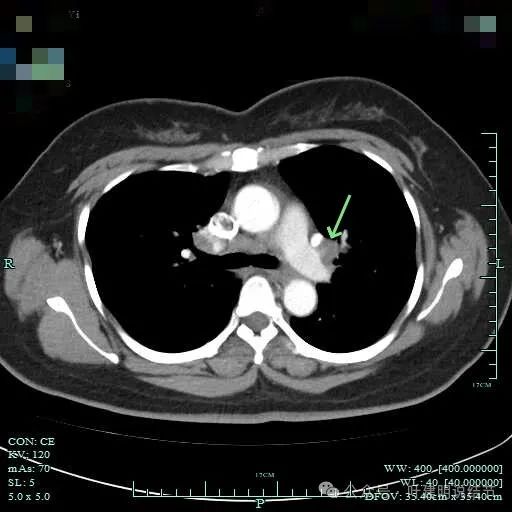

下肺静脉旁肿大淋巴结。

肺门部明显肿大淋巴结。

右侧肺门与纵隔肿大淋巴结